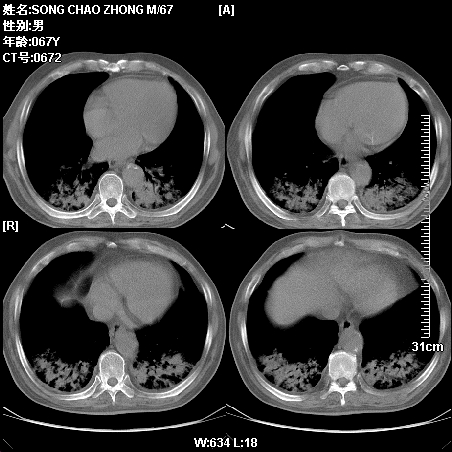

标题: CT14028:M59Y,这两例两下肺病变相同吗?

肿瘤科住院病人,都有食管癌史,都有放化疗治疗,两下肺病变是转移灶?还是其他原因造成?请老师指点

病例二 食管癌4个月,咳嗽咳痰,呼吸困难

第一个病例我感觉不是转移,第二个是个放射性肺炎;但两个都有纵隔淋巴结肿大,以第二个为主;请楼主参考